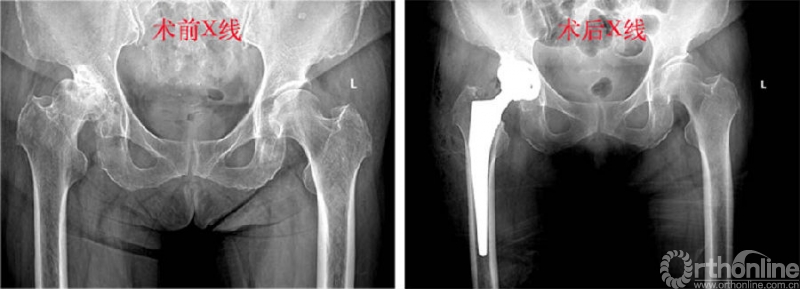

患者术前髋关节发育不良、重度骨性关节炎;VTS辅助下行THA术后双下肢长度及偏心距与对策完美匹配、髋臼外展角及前倾角与术前设计精准对应